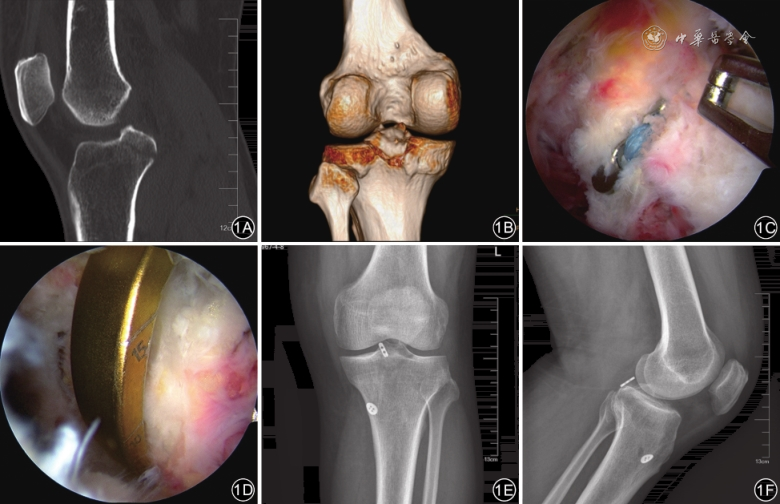

28例患者均顺利完成手术,手术时间50~90(67±8)min,术后恢复良好、切口均一期愈合,无医源性血管神经损伤、关节内血肿和感染等并发症发生。28例患者均获随访12~14个月,平均12.5个月。随访期间复查X线显示骨折均愈合,无骨折移位,未见固定物松动、脱落或断裂。骨折愈合时间2~4(2.5±0.6)个月。随访期间,2例患者屈膝受限10°、屈膝0°~125°,1例轻度伸膝受限、伸膝10°~135°,嘱患者加强功能锻炼后,仍残留少许伸屈膝受限,但无自觉症状;1例膝关节后方不适,在康复科物理治疗后,症状缓解。其余24例患者膝关节运动稳定性和屈伸情况均达到正常水平。术后12个月,28例患者Lysholm膝关节功能评分、IKDC评分均高于术前,疼痛VAS评分均低于术前,差异均有统计学意义(P值均<0.05),见表1。典型病例见图1。

蛛网膜下腔麻醉。患者仰卧位,大腿近端上止血带,使用传统高位前内侧和前外侧入路进行关节镜探查。若伴有半月板损伤则先行半月板成形术。关节镜由前外侧入路经PCL和股骨内侧髁之间进入后室,在关节镜监视下建立低位后内侧入路和高位后内侧入路。关节镜从前外侧入路撤出后再由高位后内侧入路进入后内关节囊,刨刀经低位后内侧入路进入后室,清除PCL止点附近血肿和部分关节囊及滑膜组织,辨别骨折端。PCL定位器角度设置为50°,经高位前内侧入路进入后室,尖端位于撕脱骨块的中心,由后向前施加应力将骨折块复位。在胫骨结节内侧2 cm处做一个2 cm切口,通过PCL定位器在该切口内打入引导克氏针,克氏针尖端在关节镜监视下由PCL骨折块中心穿出。移去PCL定位器换用1根4.5 mm空心钻经引导克氏针建立骨隧道,一旦空心钻穿破骨碎片皮质,移去引导克氏针和空心钻。用抓线钳将TightRope袢钢板引导线经胫骨结节内侧小切口由骨隧道远端送入,再用另一把抓线钳经低位后内侧入路将引导线拉出。用力牵引TightRope袢钢板引导线,在高位后内侧入路关节镜监视下见TightRope袢钢板长条状纽扣由骨隧道近端拉出,对另一条牵引线稍稍施加拉力将纽扣翻转,然后对TightRope袢钢板远端施加拉力,见长条形纽扣收紧压覆在PCL骨折块上完成复位。屈膝90°,拉紧TightRope袢钢板胫骨尾线,见远端的圆形纽扣紧贴于胫骨表面后,打结固定。术毕行后抽屉试验和Lachmann试验均为阴性,缝合切口。